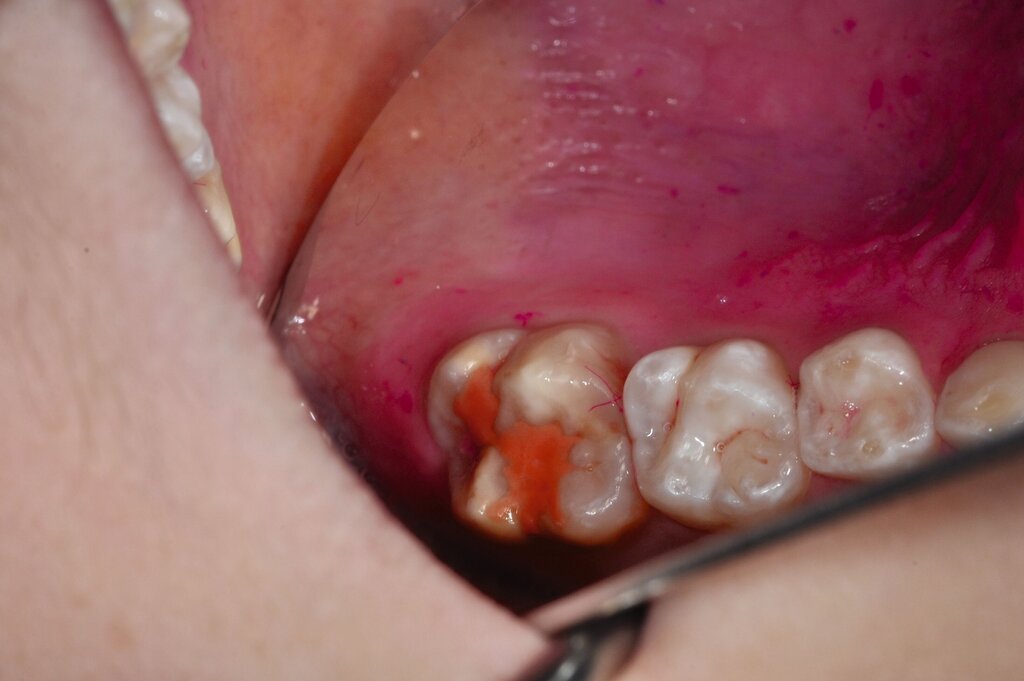

Der Vorteil der Methode ist, dass die betroffenen Zähne auch ohne Lokalanästhesie und Präparation versorgt werden können. Die temporäre Versorgung ermöglicht es, die Patienten an die zahnärztliche Behandlung zu gewöhnen. Häufig führt diese temporäre Versorgung auch zu einer Reduktion der Hypersensitivität der MIH-Zähne. Nachteil der GIZ-Versorgung ist das Risiko einer Füllungsfraktur oder eines vollständigen Verlusts der Füllung (Abbildung 4). Aktuelle Erhebungen bestätigen eine Erfolgsrate von über 80 Prozent nach einem bis zwei Jahren [Durmus et al., 2021; Mahfouz et al., 2025].

Der Behandlungsfall (Abbildung 4d) veranschaulicht die Schwächen des Verfahrens. Wird das Angebot der regelmäßigen Kontrollen nicht wahrgenommen, so droht bei Verlust der Füllung die Kariesprogression. In dem vorliegenden Fall konnte jedoch eine endodontische Maßnahme vermieden und durch die selektive Kariesentfernung die Zahnhartsubstanz weitestgehend erhalten werden.